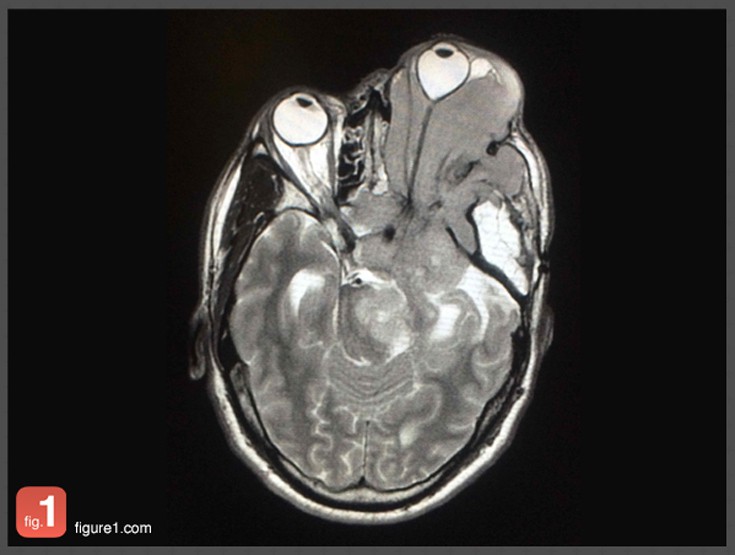

Μέσα σε τουλάχιστον 24 μήνες, το λεγόμενο «Instagram για γιατρούς» έχει δεχτεί εκατοντάδες χιλιάδες ενεργούς χρήστες που έχουν ανεβάσει πάνω από δυο εκατομμύρια τέτοιες φωτογραφίες που βλέπετε-οι περισσότερες είναι συγκλονιστικές που μόνο γιατροί μπορούν να δουν χωρίς να σοκάρονται (έχουμε επιλέξει για το θέμα αυτό τις πιο ανώδυνες)-, από σπάνιες ή περίεργες παθήσεις.

Η εφαρμογή, που ονομάζεται Figure 1, επιτρέπει σε γιατρούς από όλο τον κόσμο να ανεβάζουν ανώνυμα φωτογραφίες από τις πιο περίπλοκες ιατρικές υποθέσεις τους σε μια κοινή φωτογραφική πλατφόρμα με στόχο την ανταλλαγή πληροφοριών και συμβουλών.